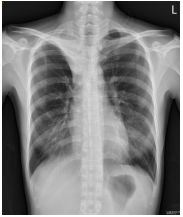

1. A 39-year-old man had this chest X-ray on his health exam. No any clinical symptoms.